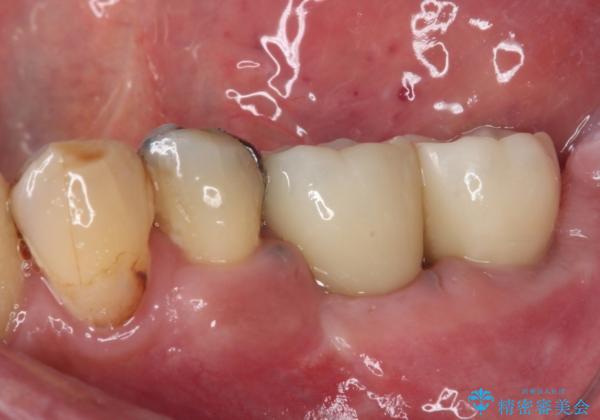

奥歯で噛みたい インプラントによる欠損補綴治療

- 抜歯をしたものの、インプラントにするか入れ歯にするか悩んでいるうちに2年以上経過してしまったとのことで来院された患者様です。

自分の歯のように噛めるようにしたいとのことで、インプラントによる欠損補綴治療を行うこととしました。

インプラントにはストローマン社のSLActiveを使用し、埋入から補綴までおよそ3か月と、短期間で治療を進めることができました。